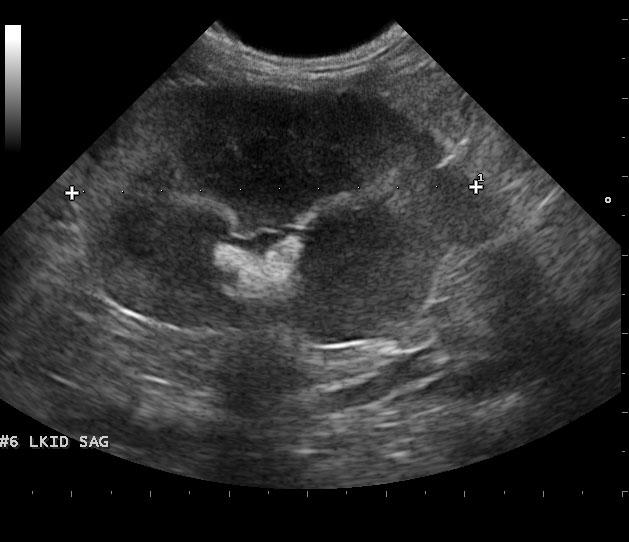

The left kidney was enlarged and measured 5.4 cm with pyelectasia and ill defined fat. Decreased corticomedullary definition was noted with focal capsular expansion at the caudal pole. The right kidney was also moderately to severely enlarged with corticomedullary and pelvic calculi. Loss of corticomedullary detail was noted. Minor subcapsular halo formation was noted with periserosal inflammation. The urinary bladder presented multiple small calculi measuring 0.1-0.3 cm. Mesenteric lymph nodes were enlarged and measured 1.5 cm and 1.8 cm. These lymph nodes were significantly hypoechoic, yet architecture was not distorted at this point. Hyperechoic reactive fat was noted.